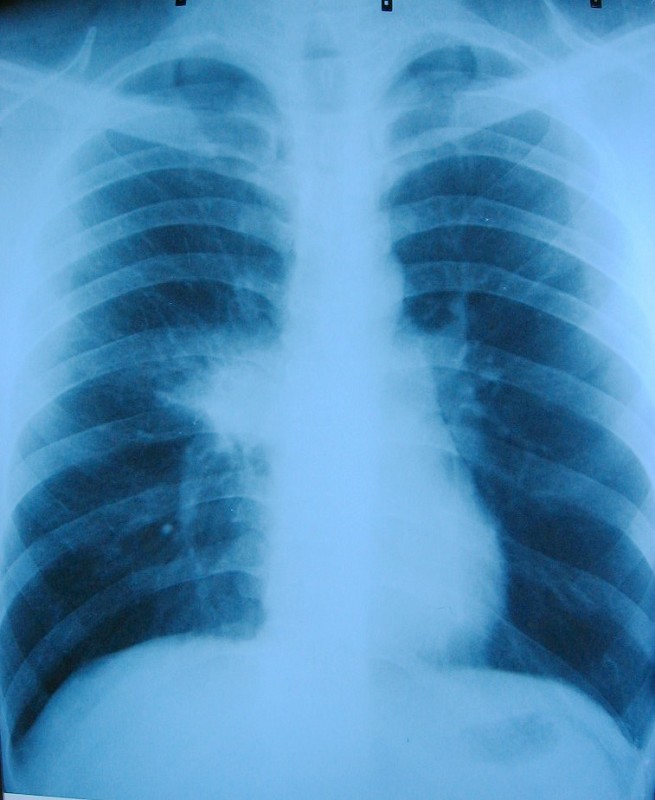

以下是引用谨言慎行在2009-4-24 16:23:00的发言:[br]考虑右肺前段肺炎。治疗14天复查。必要查ct除外占位性病变。

以下是引用随光逐影在2009-4-24 19:40:00的发言:[br]考虑右肺上叶前段肺炎。建议:1)正规抗炎治疗后复查。2)必要时行ct扫描检查排除肿瘤性病变。